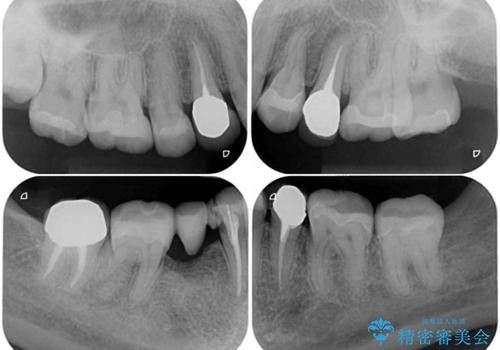

- クラウンから金属の土台が見えてきてしまったとのことで、作り替えを希望して来院された患者様です。

前歯や金属が露出している歯、痛みを感じる歯を中心に、オールセラミッククラウンにて補綴治療することとしました。